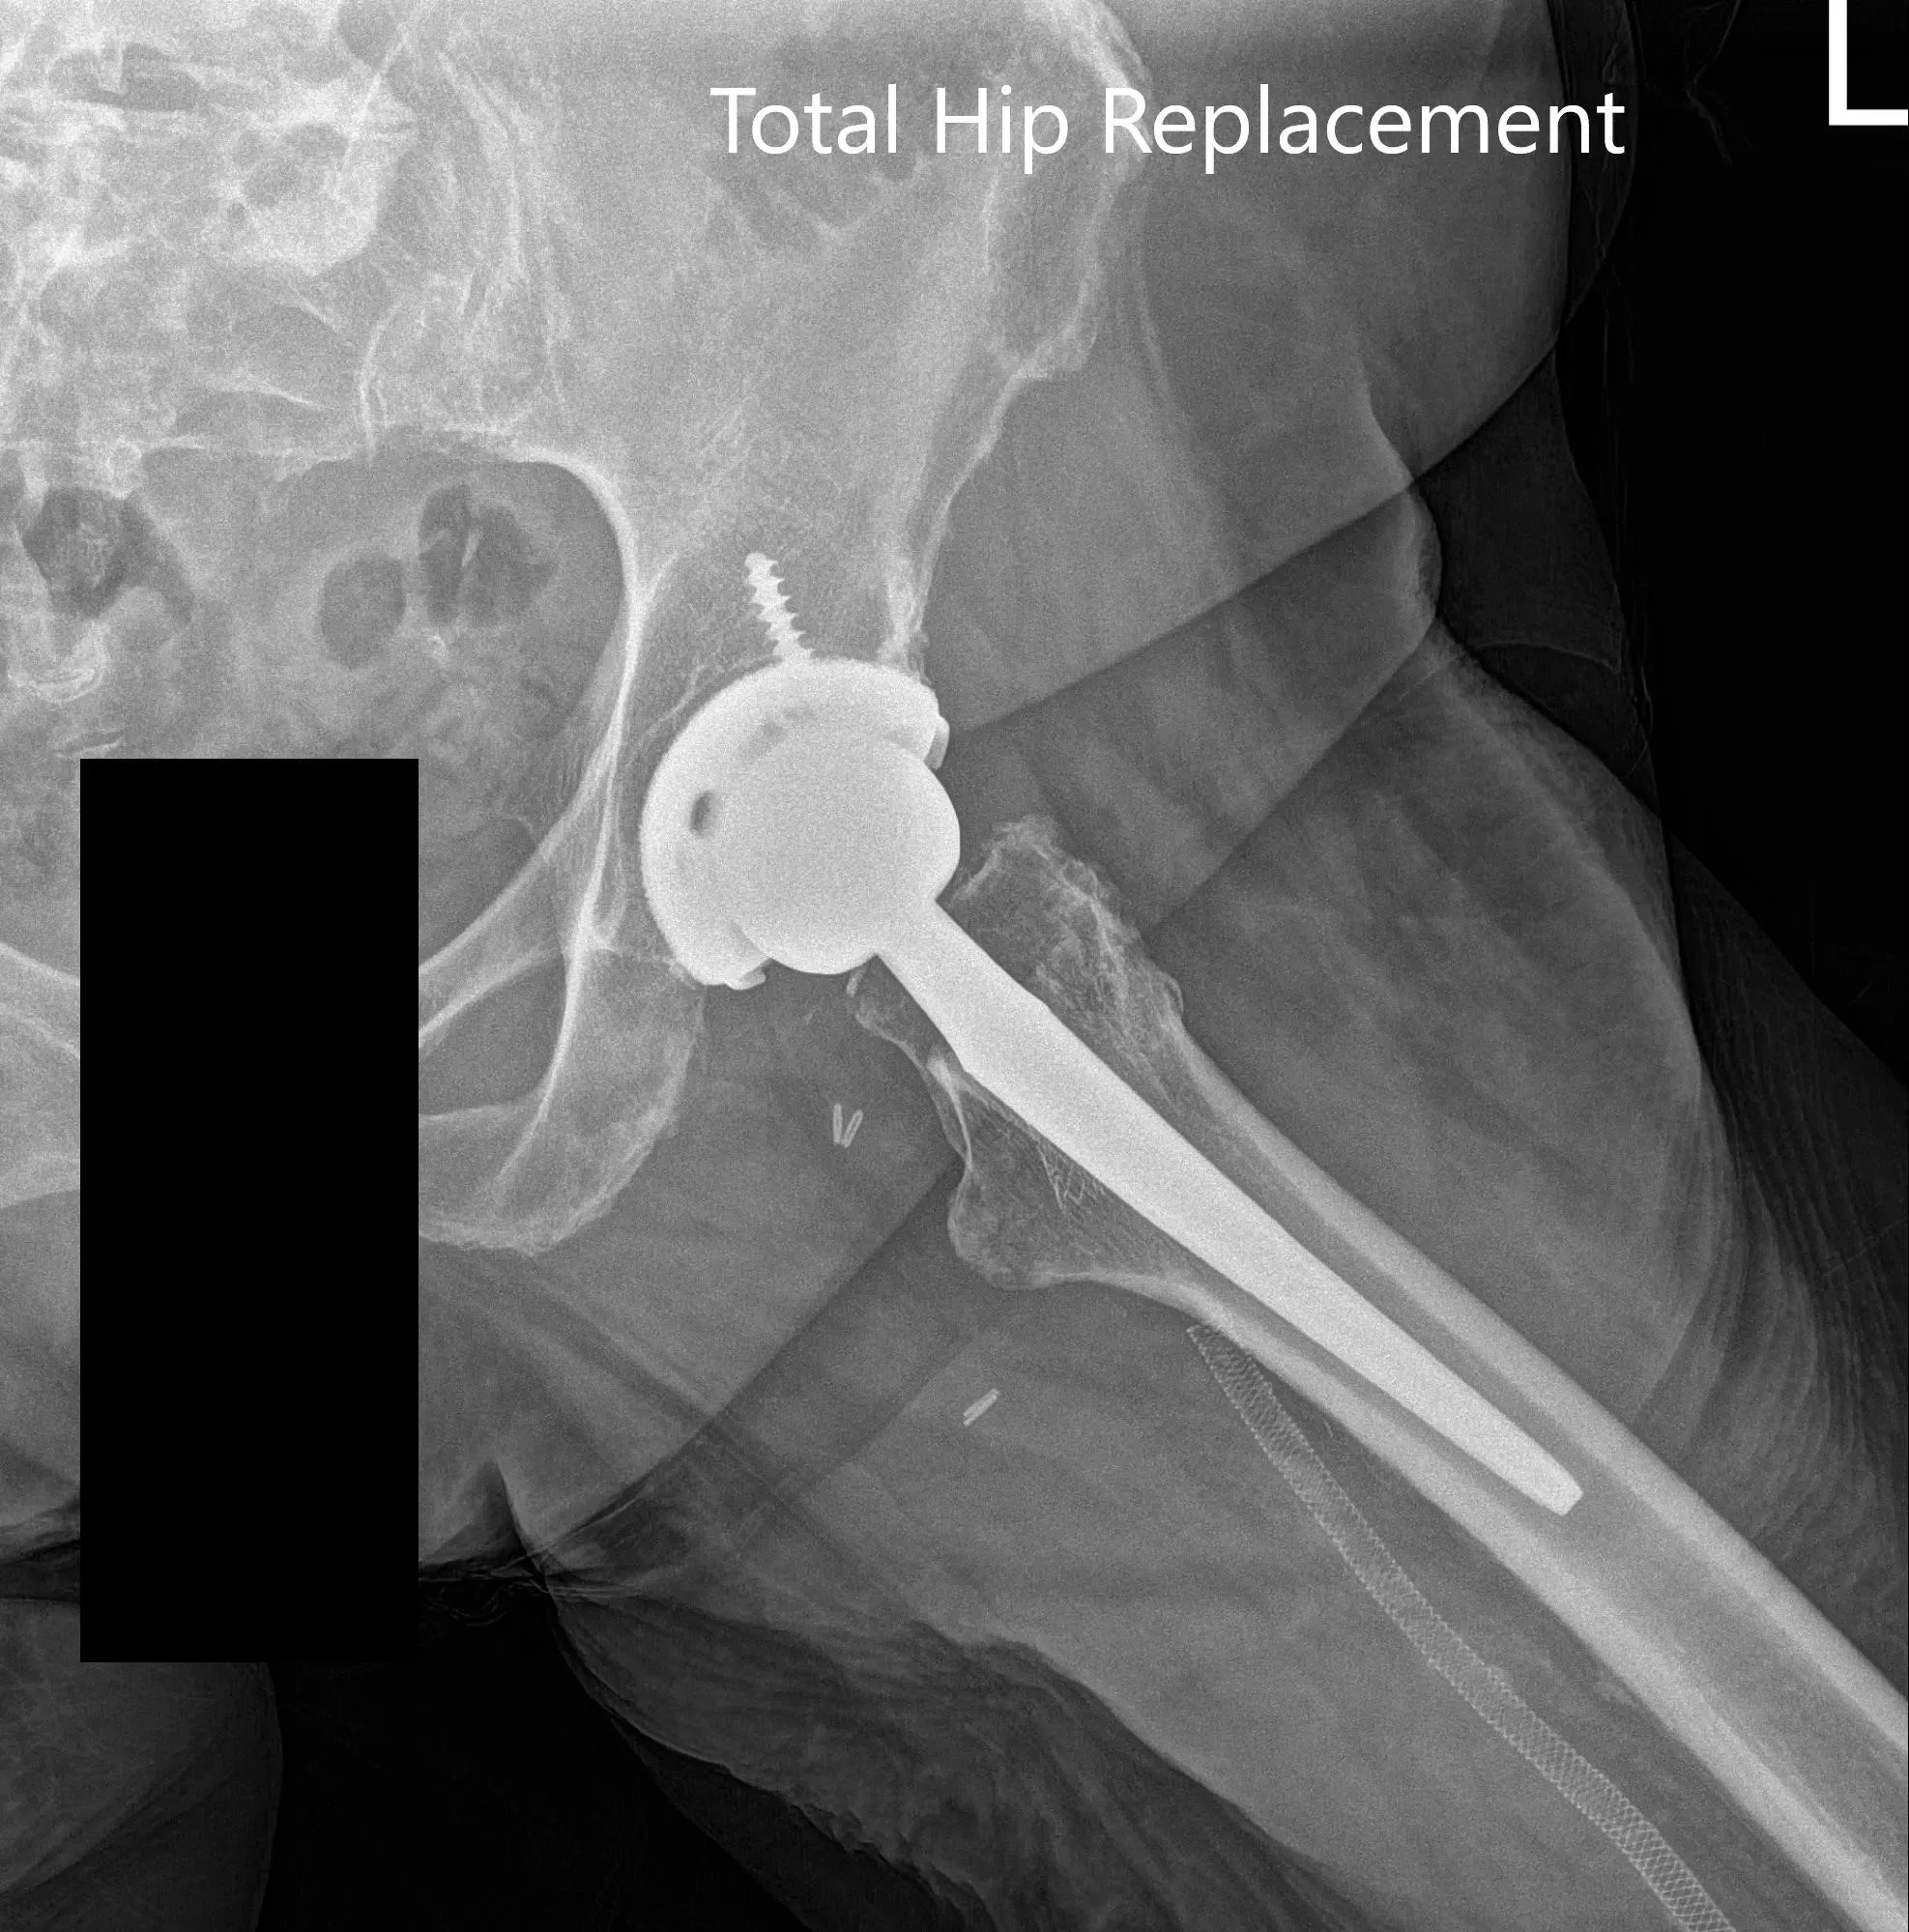

Imágenes de rayos X postoperatorias que muestran imágenes AP y laterales

La recuperación postoperatoria fue excelente, con el dolor bien controlado con medicación. Le empezaron con aspirina 325 mg para la profilaxis de trombosis venosa profunda. Se permitía la carga de peso tolerada con soporte. Las grapas de la herida quirúrgica del paciente fueron retiradas sin incidentes. Su fisioterapia se centró en el entrenamiento de la marcha, el fortalecimiento de músculos y ejercicios de rango de movimiento.

Tras tres meses de seguimiento, mostró un rango completo de movimiento sin dolor. Se quejaba de una leve rigidez y le aconsejaron continuar con la fisioterapia y el programa de ejercicio en casa. Había vuelto felizmente a las actividades que disfrutaba. La mayor movilidad le hizo feliz y más inclusivo en su familia.